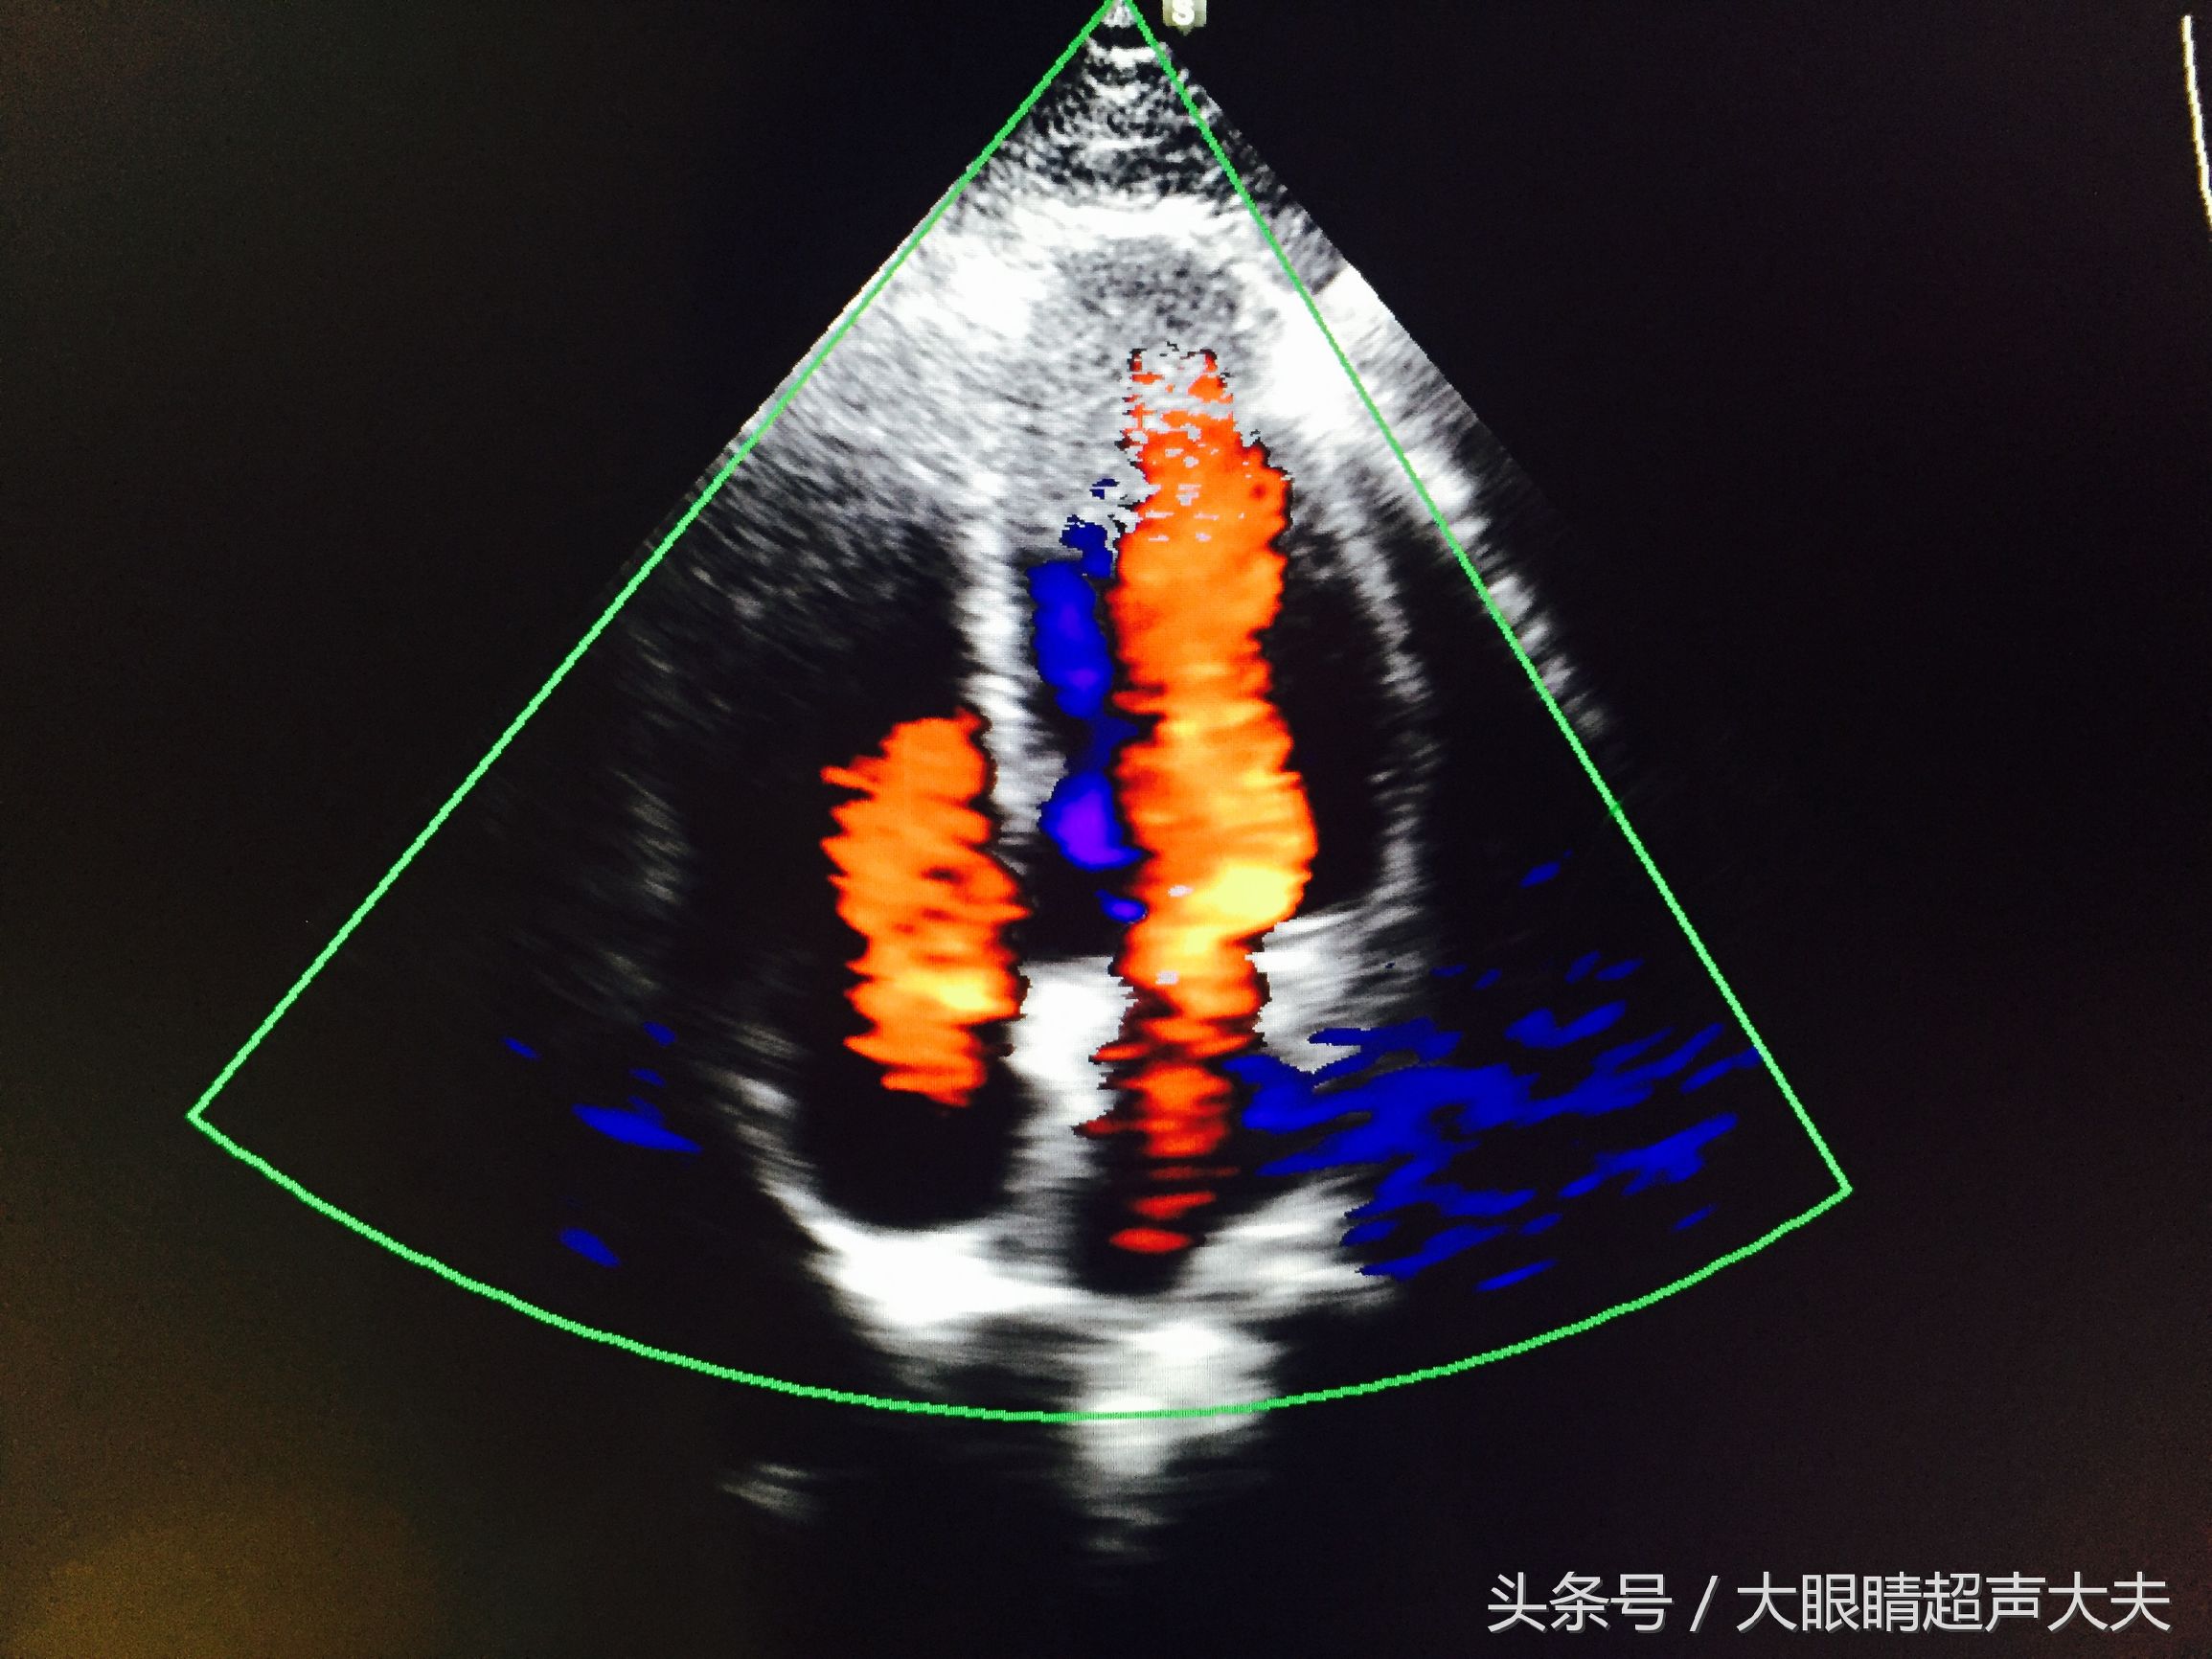

各种情境一样。而真正的彩超,是在黑白B超图像的基础上,当大夫需要知道某个脏器/部位的血供情况,某个结节/病变部位的血供情况(如上图中就是显示的一个甲状腺癌的血流情况),某根血管的走形情况的时候,大夫就会打出一个框框来,在框内会显示红蓝色的血流图像。而

这里的红蓝色并不是我们中学学生物时学到的红色代表动脉血,蓝色代表静脉血,不是的。这里的红蓝色代表着血流的

方向

。颜色的亮度代表着血流速度。医生再通过机器打出频谱,经过测量,可以得到某血管的血流速度,血流阻力,压差……等等各种指标。所以,彩超可以在黑白B超的基础上,又给医生提供了更多的信息,这样更加有利于疾病的诊断。